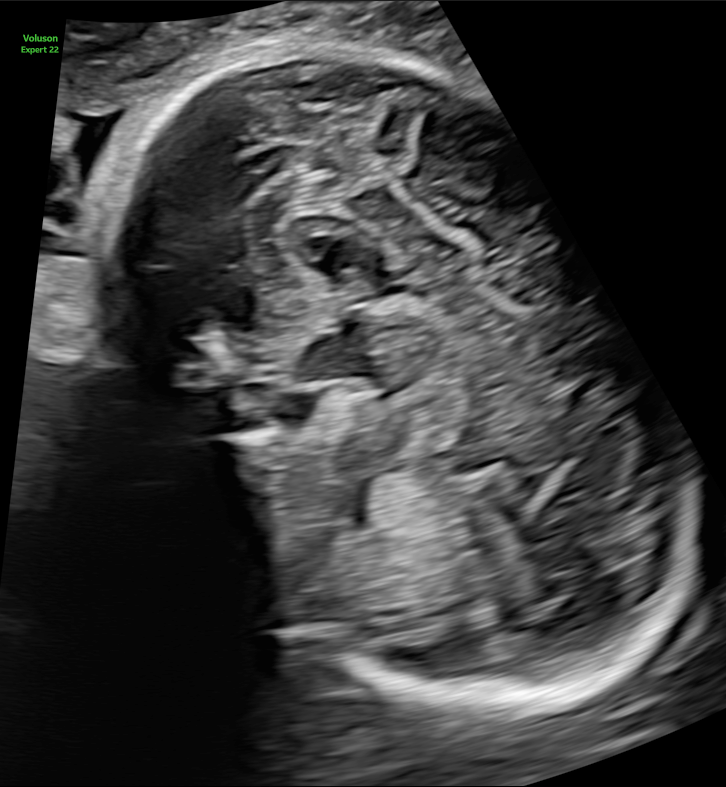

医療課題の解決に取り組むヘルスケアカンパニー、GEヘルスケア・ジャパン株式会社(以下GEヘルスケア・ジャパン、本社:東京都日野市、代表取締役社長兼CEO:多田荘一郎)は、産婦人科向け超音波画像診断装置「Volusonシリーズ」の最新フラッグシップモデル「Voluson Expert 22」の販売を7月19日より開始しました。これに伴い、2022年8月5日(金)より開催される第74 回日本産科婦人科学会学術講演会にて同製品の初出展を行います。

この度、GEヘルスケア・ジャパンが日本にて提供を開始する新製品「Voluson Expert 22」は、より良い診断を行うことができるよう、常に考えを巡らせ、女性医療の第一線に立つ産婦人科医が抱える課題の解決に取り組むとともに、高度化するニーズにどこまでも応えられるように開発された、最新モデルです。基本性能を大幅に引き上げ、早期発見・介入に貢献するクリニカルツールや、一日の検査を精度良く効率的に実施いただくための自動化ツールの搭載によって、より健康な女性の未来の実現に貢献します。

Voluson Expert 22では、より膨大な情報を高速処理可能な次世代エンジンLyric Architectureを搭載したことで、ソフトウェア制御されたビームフォーミングを実現。ハードウェア制御の限界を超え、格段に向上したペネトレーション、分解能、フレームレートを提供します。また、従来のVoluson製品では活用できなかった、新たなレベルの画像処理が可能となり、分解能に特化したイメージングモードから、深部感度に特化したイメージングモードまで、観察条件に大きく左右されることのない、明瞭な画像を提供します。